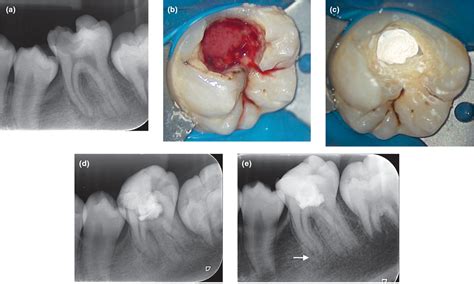

When a dentist evaluates tooth pulp exposed, they will look for the viability of the nerve. Depending on the severity of the damage, the treatment plan will vary. Below is a summary of the most common professional interventions.

Condition Severity Primary Treatment Goal

Mild Exposure (Small) Direct Pulp Capping To protect the pulp and encourage healing.

Moderate Decay Root Canal Therapy To remove infected tissue and save the tooth.

Severe Damage/Fracture Tooth Extraction To prevent infection from spreading.

When you visit the dentist, they will likely take X-rays to assess the extent of the damage. If the pulp is inflamed but not yet necrotic (dead), the dentist might attempt to save the pulp through a process known as pulp capping, where a biocompatible material is placed over the exposed area to seal it off. If the pulp is already infected, a root canal is the standard of care to remove the bacteria, disinfect the chamber, and restore the structure of the tooth.